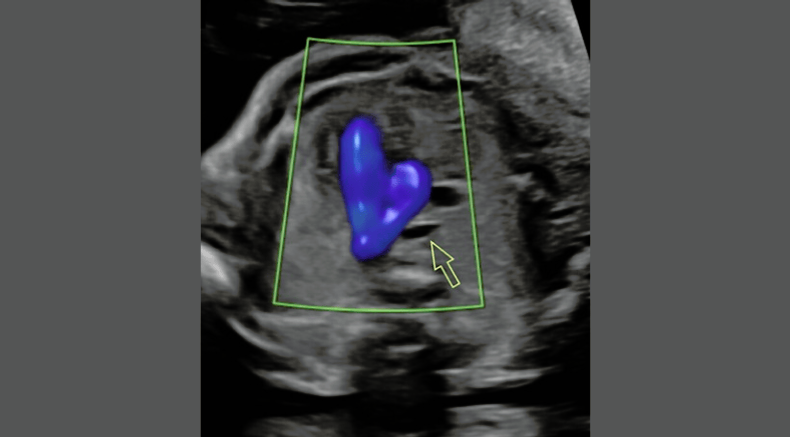

Four chamber heart view

Abu-Rustum, R. (2025, September 14-17th). The fundamental four chamber view: what you might see and what you might miss [Workshop]. 2025 ISUOG World Congress, Cancun, Mexico.

Apical four chamber heart view with colour doppler during diastole

Four chamber view of the fetal heart with colour doppler during diastole